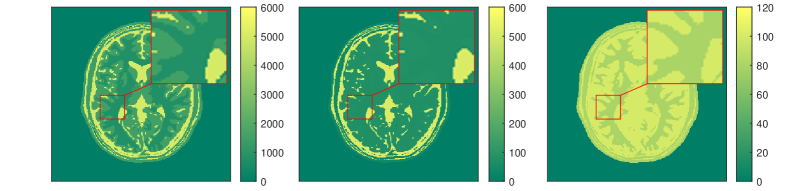

The results for each of the above mentioned algorithms can be found in Figures 3 and 4. We use the MRF reconstruction as initialization for the L-M algorithm, and compare that with the result of the BLIP algorithm when using a relatively refined dictionary. The advantage of integrated-physics approaches is evident by checking the reconstructions in Figure 3 as well as quantitatively by looking at the error maps in Figure 4. In this example, we have used a time series of the 1/8 Cartesian-subsampled k-space data (Fourier coefficients of magnetizations) of length 40. In the original MRF algorithm (typically requiring a large time series of k-space data), this test setting is far from yielding a reasonable result, while BLIP has improved a little by enforcing the projection to the Bloch manifold. But still one observes deficiencies. The method with integrated physics, however, appears to be efficient and it returns the best results among the three methods.

The results in [57] show that the proposed integrated physics model can work well for settings where an explicit solution formula for the Bloch equations is available. However, in most cases (excitation sequences) the Bloch equations have no explicit solution formula. In addition, from a practitioners perspective the Bloch equations appear to be only a simplified mathematical model under some assumptions. As in reality these assumptions are often not realistic, one indeed requires a more complex model. In this vein, deep learning turns out to be a useful data-driven technique for learning or approximating such physical models. In Subsection 3.3 we will therefore discuss extracting physical laws from data.